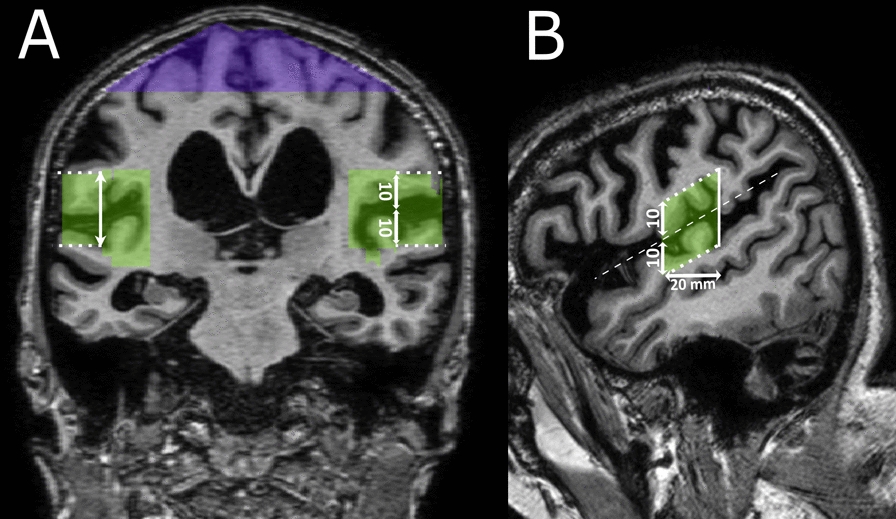

Materials and methods: By using a semiautomatic quantitative method, we calculated quantitative DESH (qDESH), defined as a ratio between CSF volumes at high convexities and Sylvian fissures. The analysis was based on three-dimensional T1-weighted images from 35 subjects with iNPH (mean age 74 yrs; 10 females) and 45 controls (mean age 72 yrs; 13 females). The interrater agreement for qDESH was evaluated by the intraclass correlation coefficient, and qDESH was compared with visual assessments performed by two neuroradiologists.